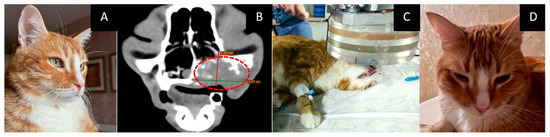

3.7. Male Cat “Semyon”

- Age: 6 years.

- Localization and size of the tumor: right femur and iliac bone; according to a CT scan, the tumor was 34 × 32 × 37 mm in size.

- Treatment except for GdNCT: four courses of chemotherapy.

- Pathological diagnosis: osteogenic sarcoma.

- The course of the disease after GdNCT: on the tenth day after NCT, the animal was eating, drinking, and feeling well. A CT scan three months after irradiation revealed an increase in the tumor size to 58 × 38 × 46 mm (Figure 7).